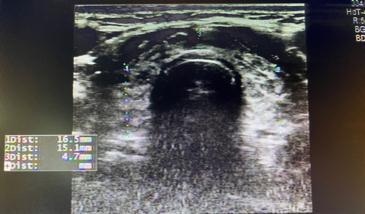

桥本氏甲状腺炎:甲状腺大小可正常,也可以呈非均匀性肿大,不过在疾病后期一般都表现为甲状腺缩小。超声图像一般分为弥漫型、局限型和结节形成型。其中结节形成型有时候经常会在体检时发现为结节而来就诊,有时候较难与恶性结节相鉴别,可以定期复查,或者超声造影或者进行结节穿刺进行进一步检查。

图片